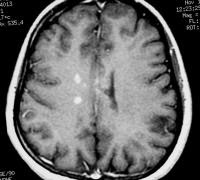

proton density–weighted MRI demonstrates multiple lesions in a

distribution characteristic of multiple sclerosis. Specifically, the

periventricular lesions and the more peripheral white matter lesions

near the gray matter–white matter junction are typical MRI findings in

multiple sclerosis.